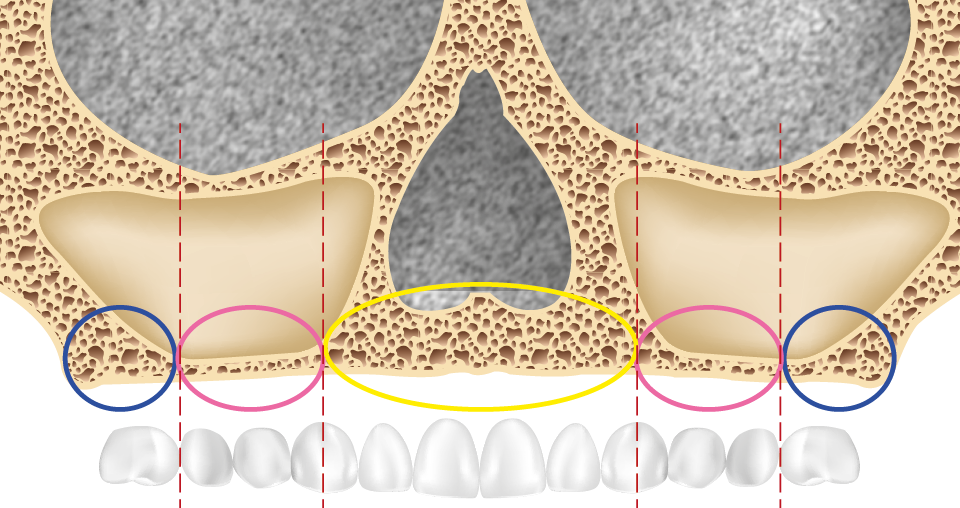

La perte des dents s’accompagne toujours d’une résorption osseuse plus ou moins importante, phénomène parfois accentué par le port de prothèses amovibles qui peuvent se révéler iatrogènes et accroître la perte osseuse. La classification de Bedrossian [1] divise le maxillaire supérieur en trois zones (fig. 1) :

- zone 1 : sous-nasale ;

- zone 2 : bosse canine (comprise entre les fosses nasales et le mur antérieur des sinus) ;

- zone 3 : sous-sinusienne.

La présence d’os dans les trois zones autorise une distribution idéale des implants avec notamment l’absence de cantilever. Quand l’os est absent ou en faible quantité dans la zone 3, le recours à l’angulation des implants distaux le long du mur antérieur des sinus est possible ; le cas peut alors être traité selon la technique « All-on-four ». En revanche, quand le seul volume osseux disponible est en zone 1, le recours à des implants transzygomatiques (ou à des greffes osseuses) est indispensable [2].